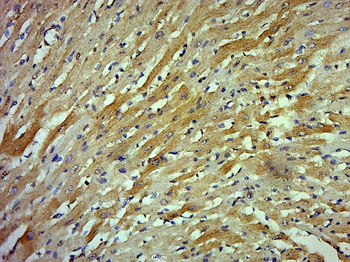

100 μl, 200 μl, 50 μl - RORC Rabbit Polyclonal Antibody [orb6888]Featured

FC, ICC, IF, IHC-Fr, IHC-P, WB

Human, Mouse, Rat

Bovine, Canine, Equine, Gallus, Porcine, Rabbit

Rabbit

Polyclonal

Unconjugated

50 μl, 100 μl, 200 μl - Featured